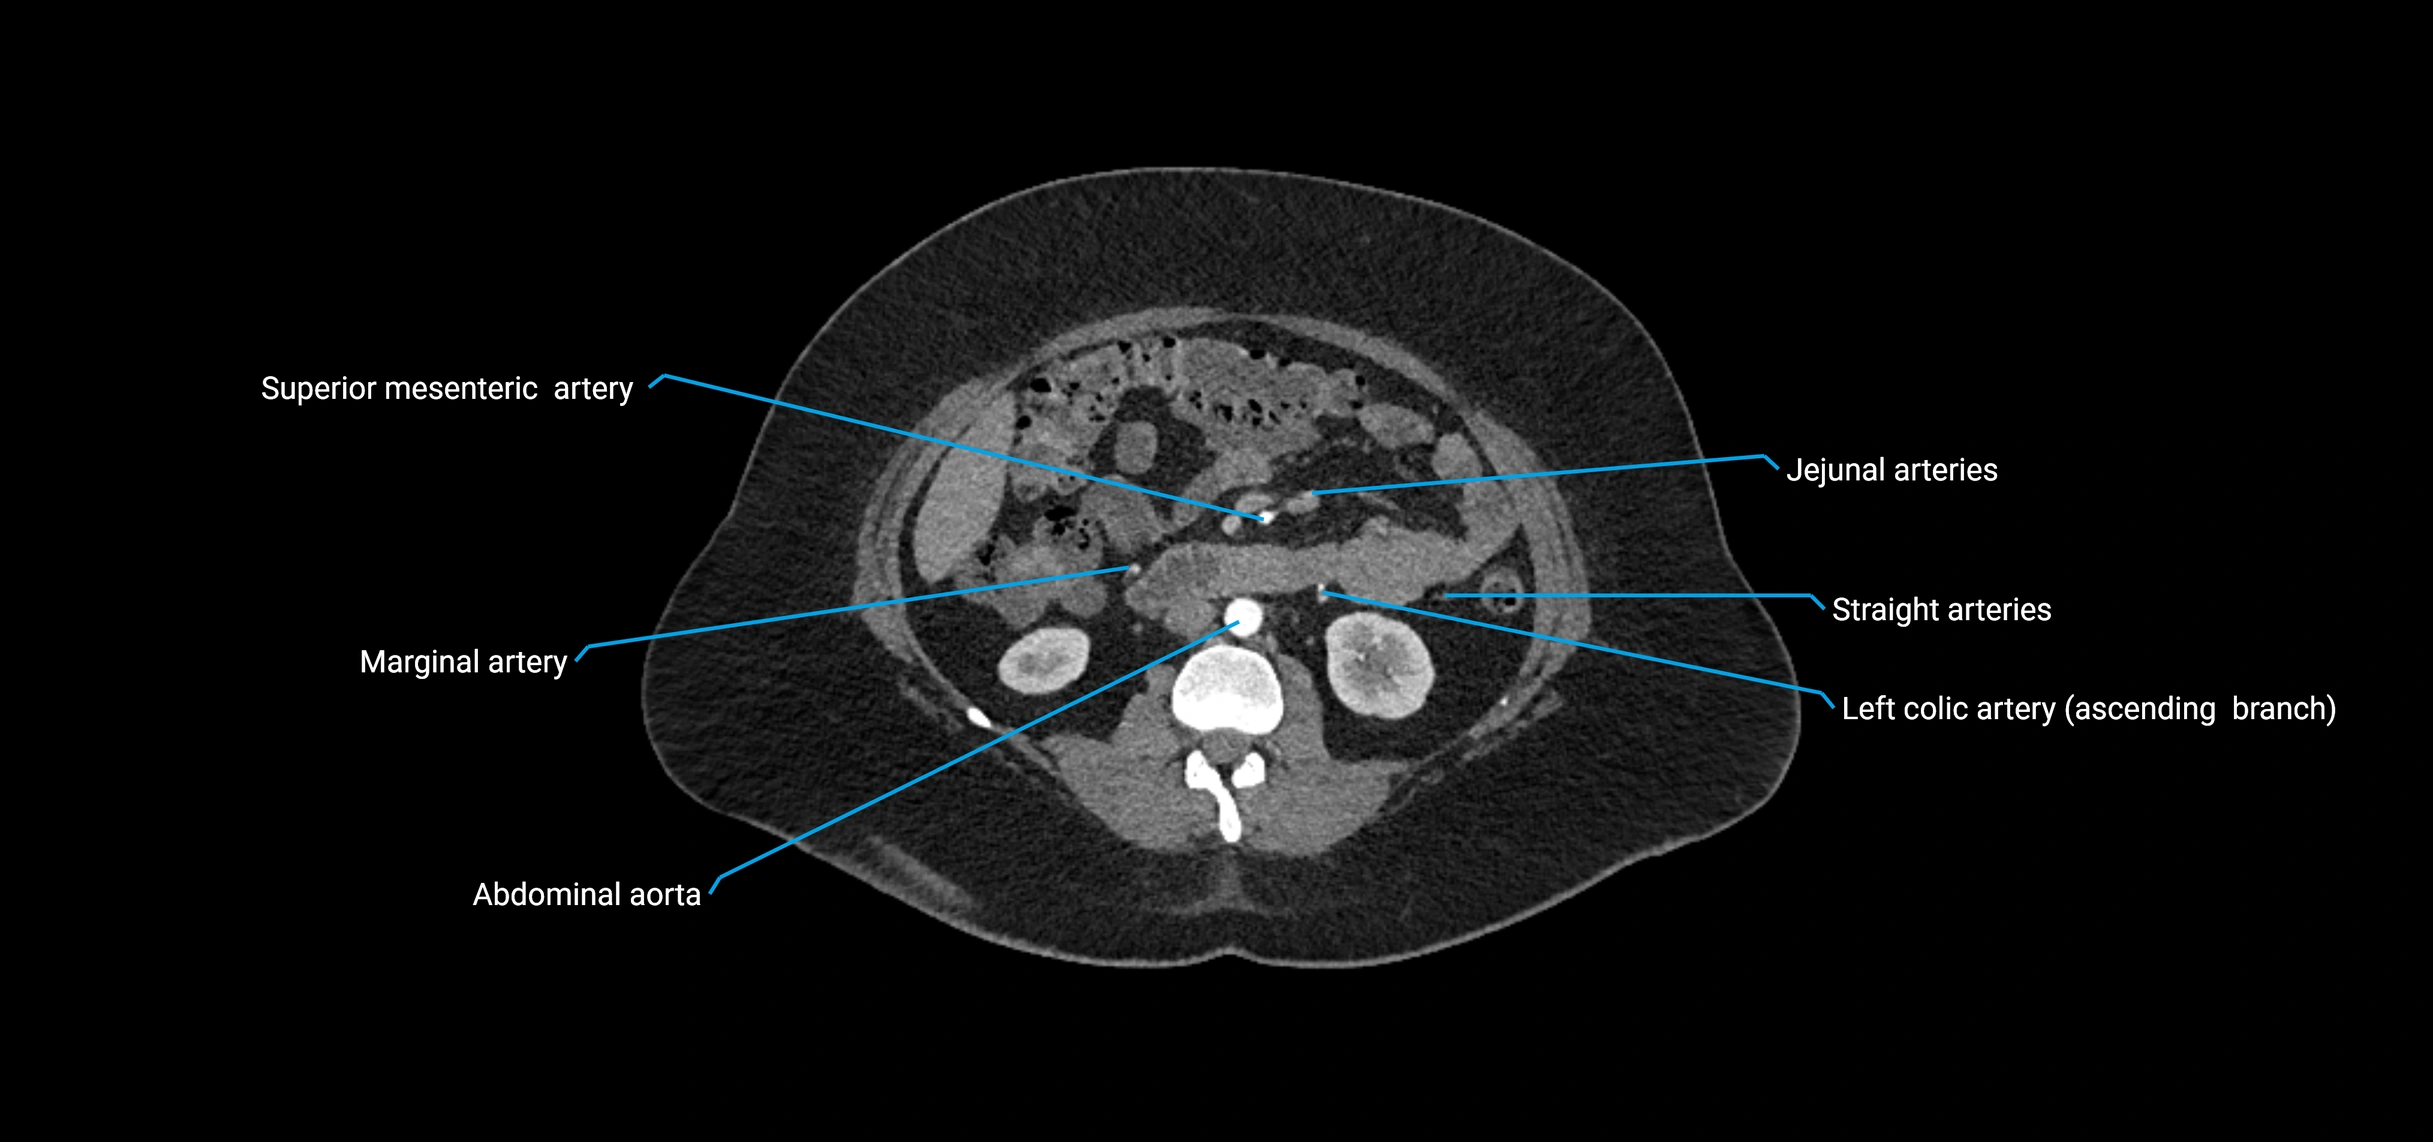

CT images

image

Contrast-enhanced CT (CTA):

• Gold standard for abdominal aortic imaging

• Provides excellent detail of lumen, wall, aneurysm, thrombus, and branch vessels

• Multiplanar and 3D reconstructions help in aneurysm measurement, stent graft planning, and dissection evaluation